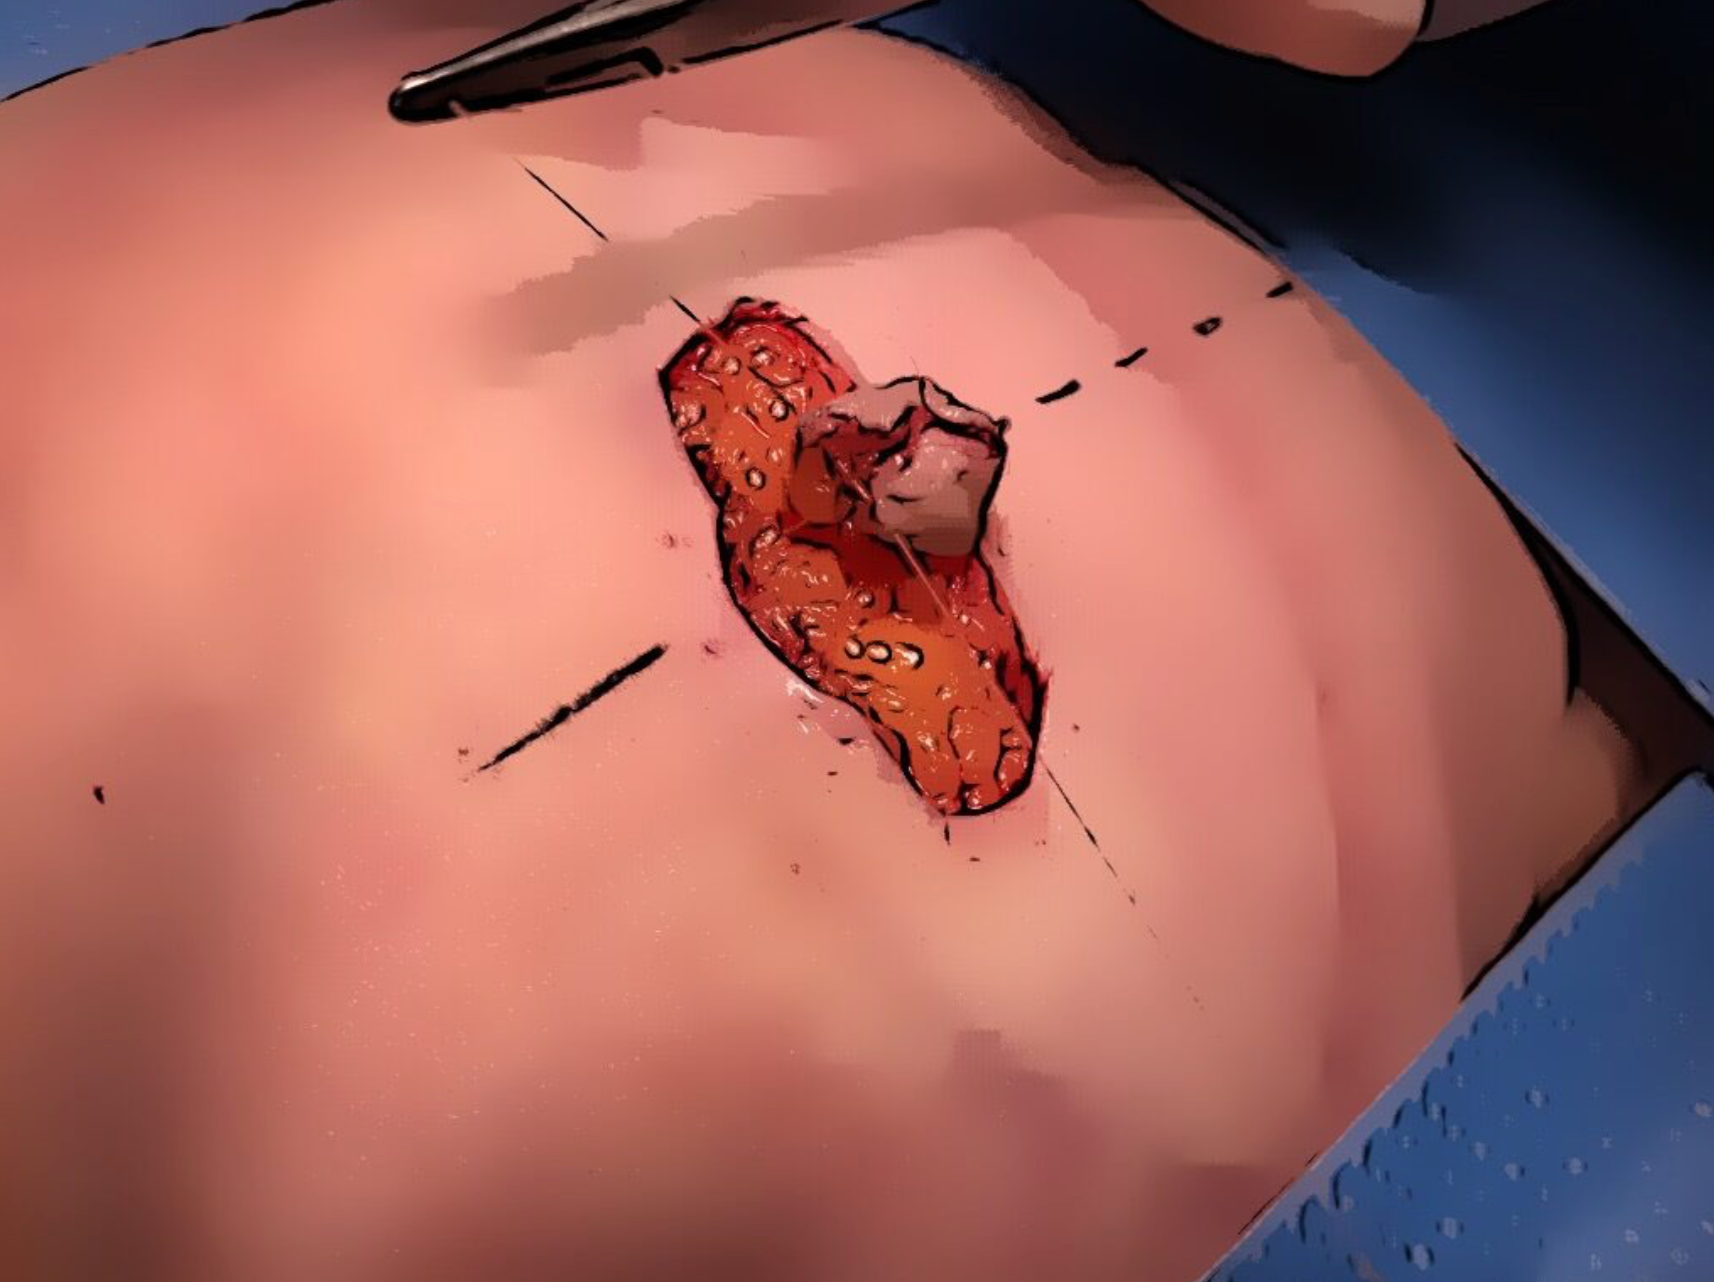

Isoleren bloedvat

Het bloedvaatje of perforant wordt voorzichtig geïsoleerd en vrij gelegd. De spieren worden niet meegenomen en blijven intact.

Volgen bloedvat

De perforant wordt volledig gevolgd tot aan het hoofdbloedvat. Dit hoofdbloedvat is de diepe epigastrische arterie en vene.